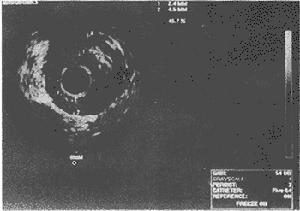

超聲心動圖查血流正常主動脈根部是3個擴張的冠狀竇,左、右冠脈分別起自左、右冠竇的竇管嵴下方。若冠脈起自對側竇、後竇、竇底部(低位開口)、竇管嵴上方1.0 cm以上(高位開口)或肺動脈,均為起源異常。常伴近段走行異常,行於主、肺動脈間者,易受壓導致心肌缺血甚至猝死。異常起源的開口常較小,且與起始部呈銳角或切線位,也易引起心肌缺血,並且此類畸形易漏誤診。